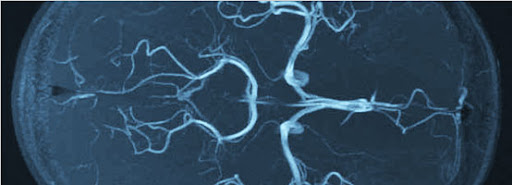

A radiopaque contrast agent absorbs x-rays and thus appears white on x-rays. It is typically used to show the following: Blood vessels. The interior of the gastrointestinal, biliary, or urinary tract. Blood flow in organs.